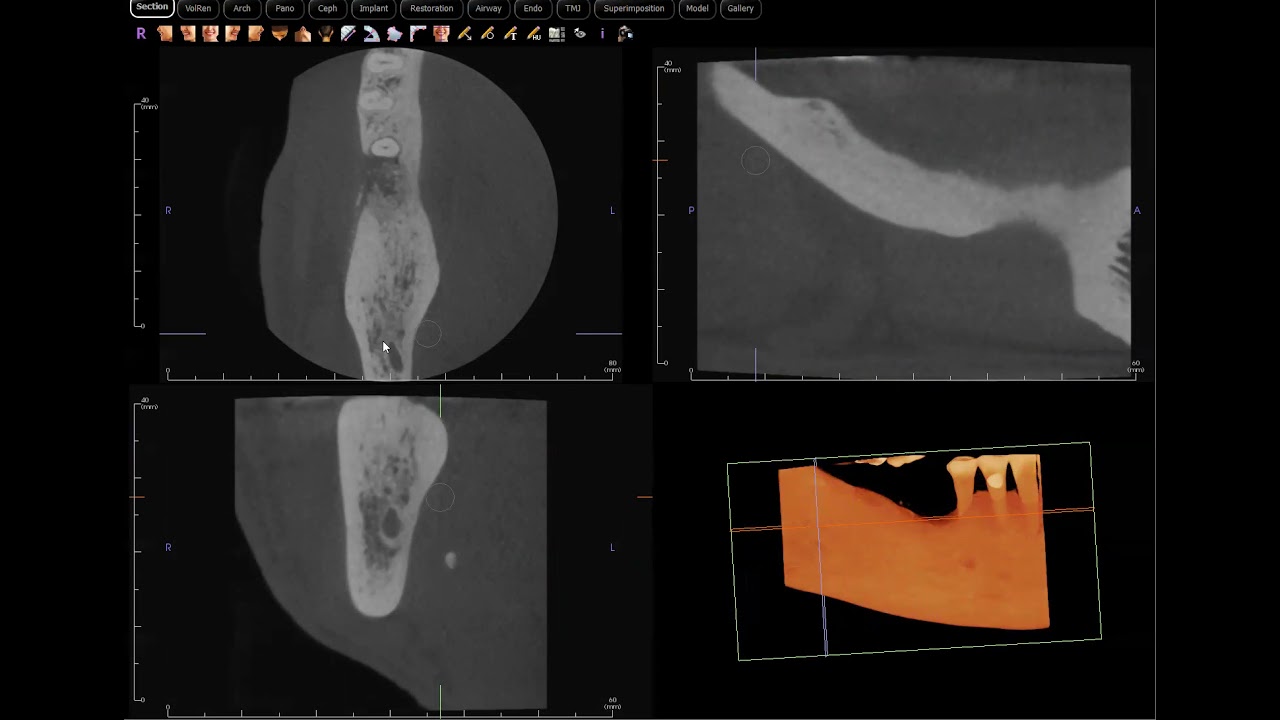

Скачать или смотреть Recurrent OKC (Odontogenic keratocyst) confirmed!

Recurrent OKC (Odontogenic keratocyst) confirmed!